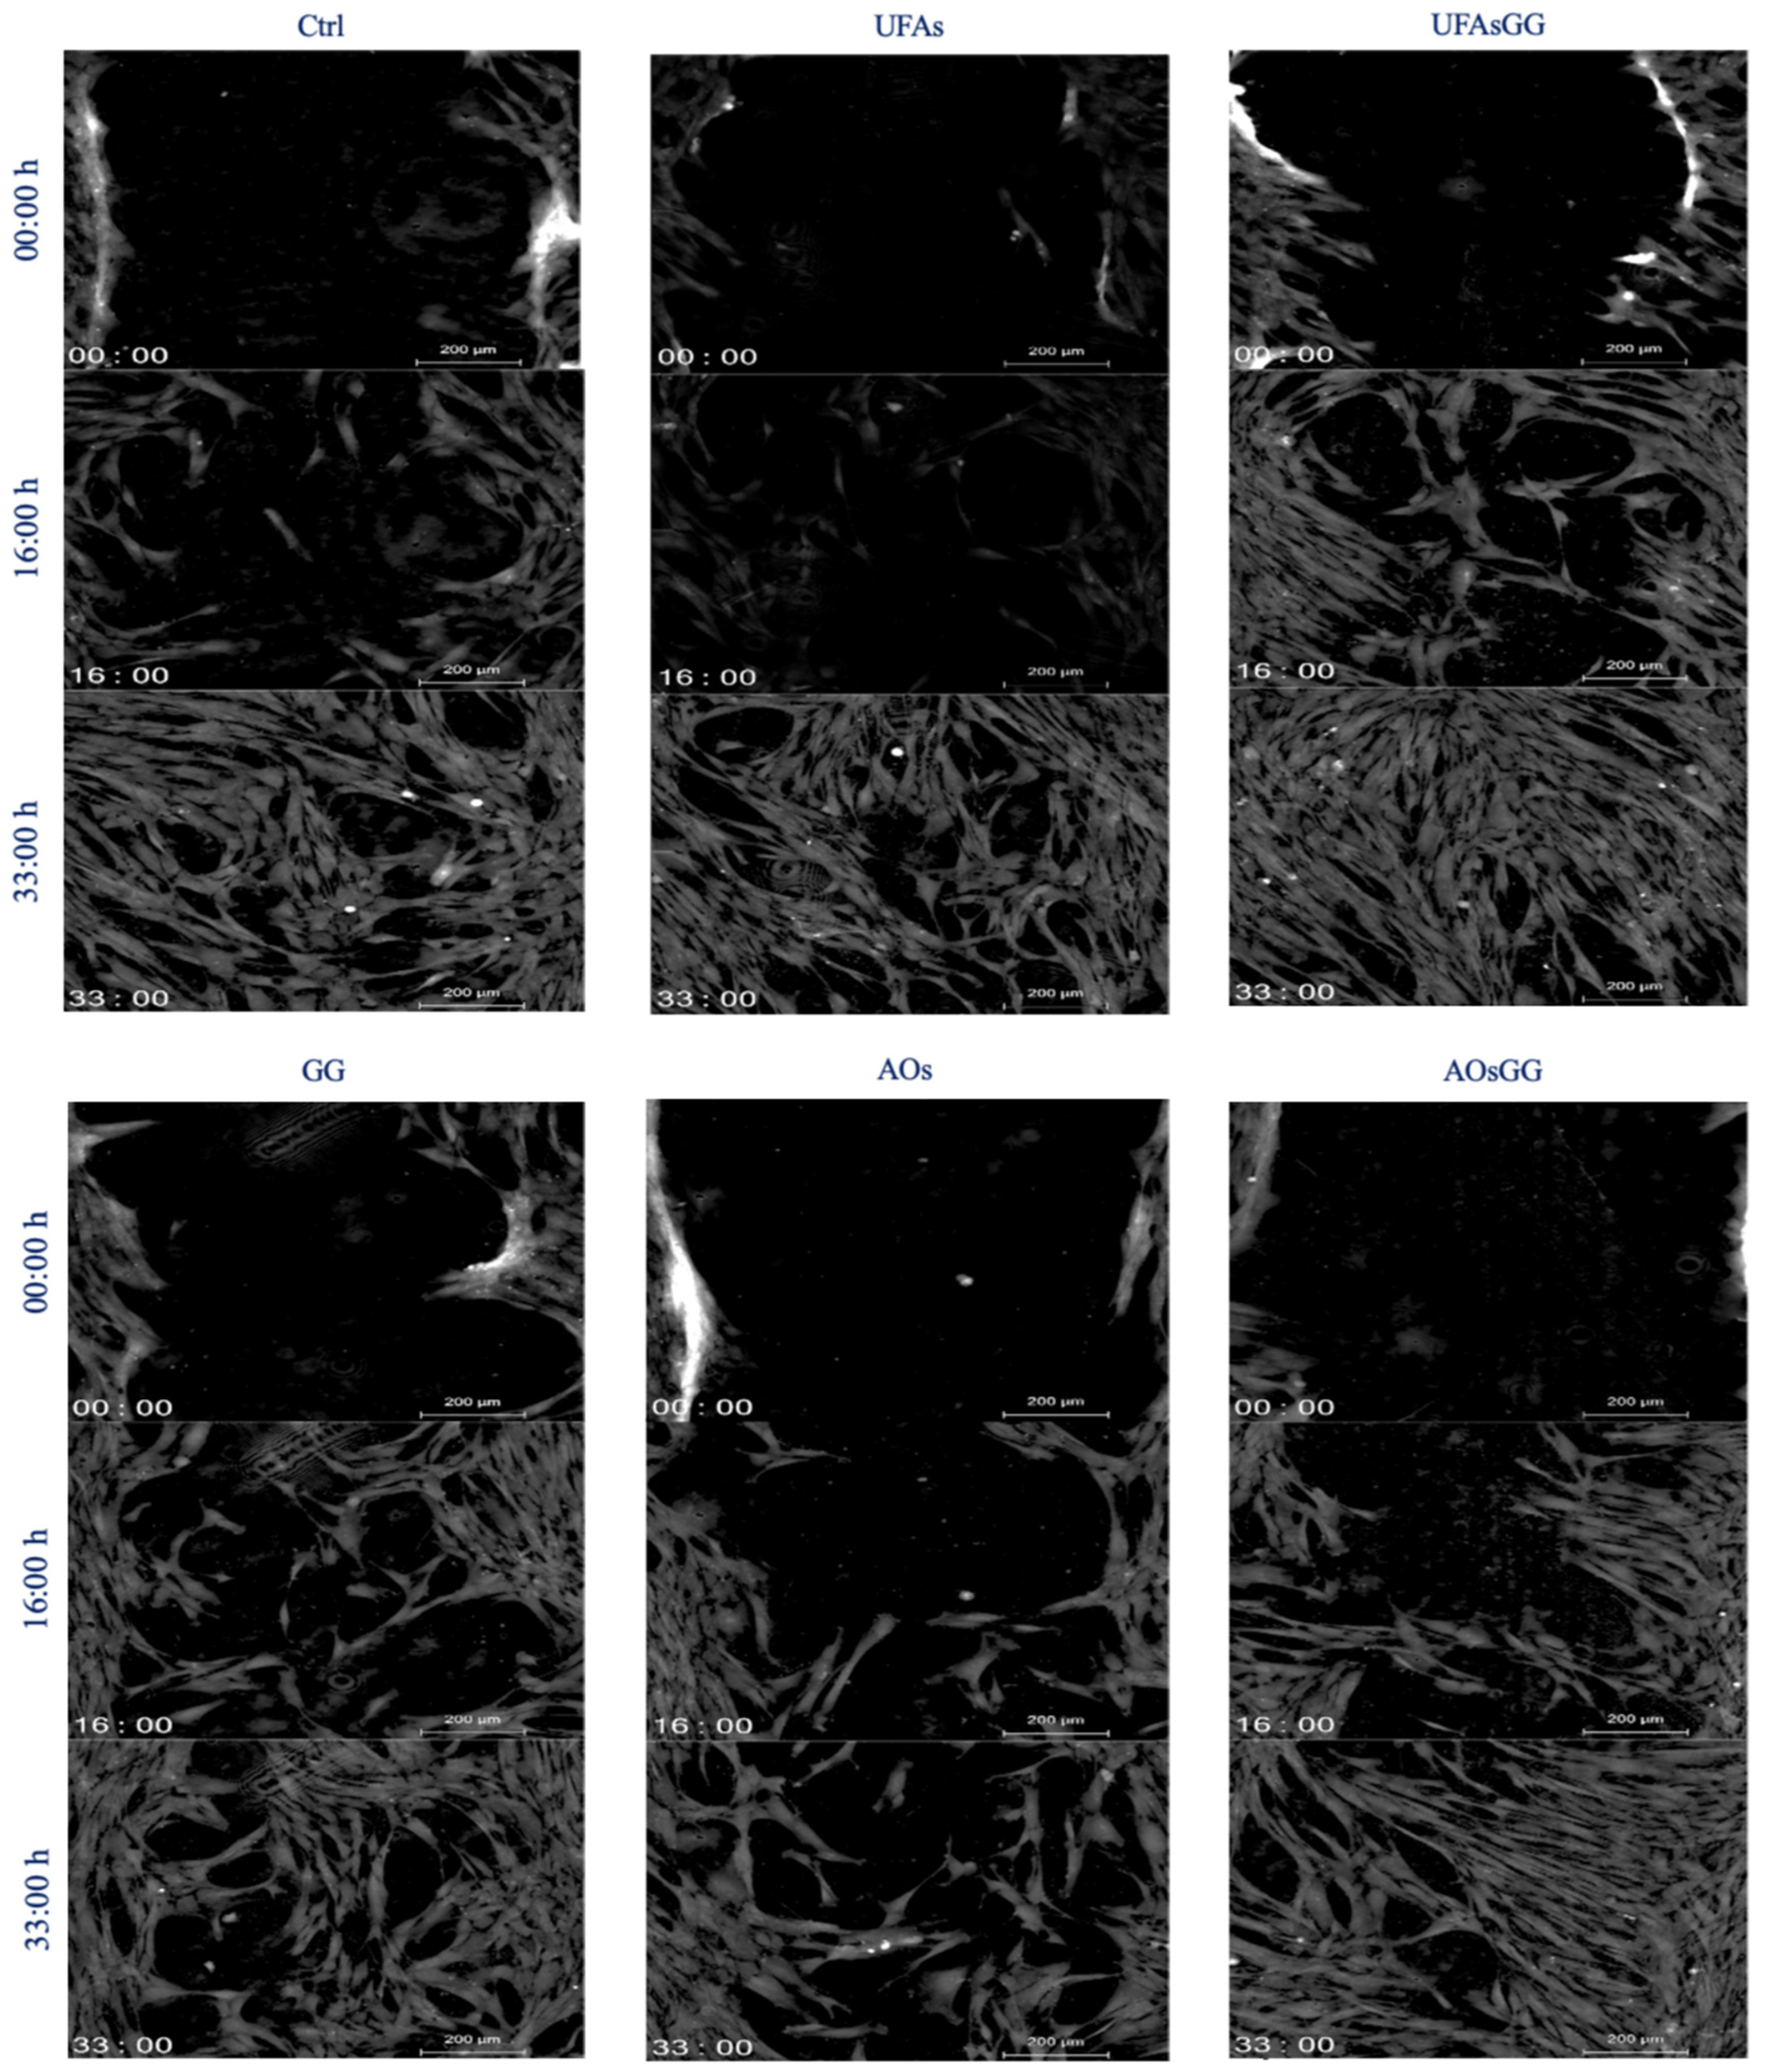

2.10. Wound-Healing Assay

3.7.2. Wound Healing Assay